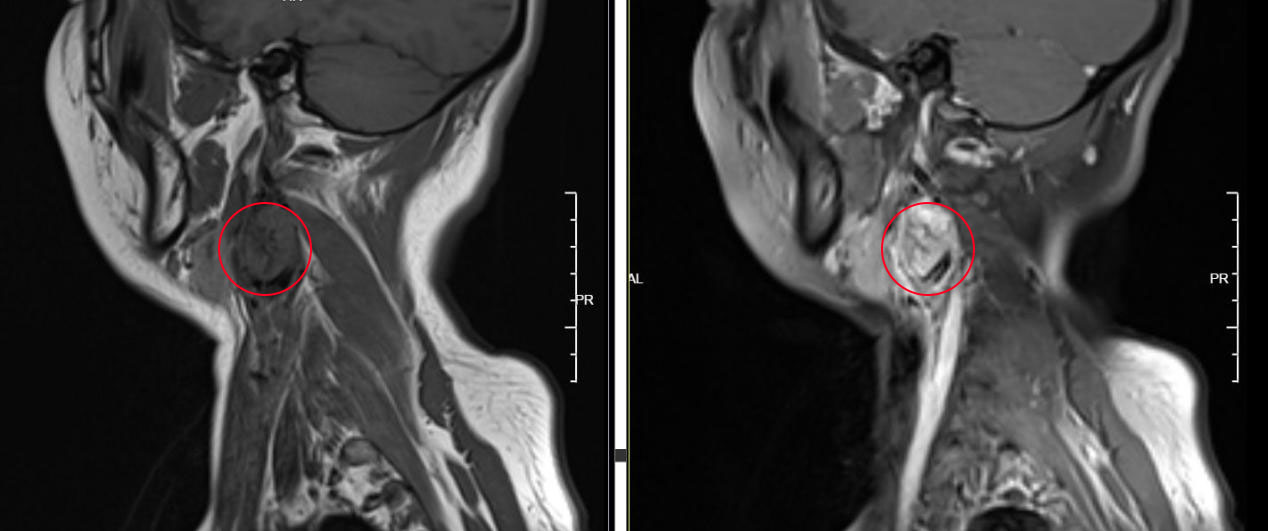

影像学是诊断颈动脉体瘤的重要工具之一。常用的影像学检查包括超声、CT扫描和磁共振成像(MRI)。超声可以提供血流动力学信息,帮助确定瘤体的位置和大小。CT扫描和MRI则可以提供更详细的解剖结构信息,帮助医生评估瘤体的形态和与周围组织的关系。